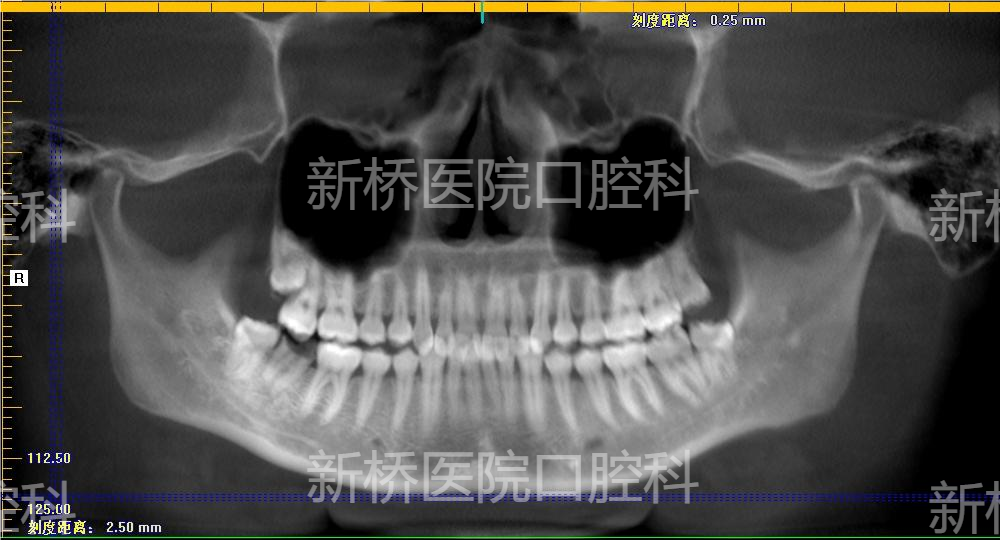

自体牙移植(auto transplantation , ATT) : 自体牙移植是将牙从一个位置移植到同一个体的另一位置,包括将埋伏、阻生、或萌出牙转移到其他缺牙部位牙槽窝内或手术制备的牙槽窝内。

本例采用3D数字化打印技术,术前模拟牙槽窝修整部位,术中用3D打印等比树脂牙试植,做到精准高效制备植入窝,减少供牙离体时间,减少供牙反复植入次数,极大减少供牙牙周膜损伤。